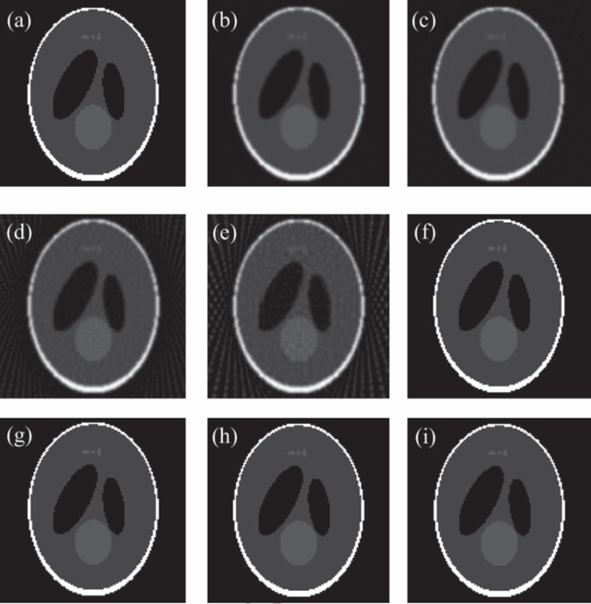

实验结果表明:与解析重建算法FDK相比,提出的算法在投影数较少的情况下,仍能获得较好的重建图像质量(见图1);与两种现有的基于TV正则化的迭代重建算法(ASD-POCS,EM-TV)相比,所提算法收敛速度提高6倍以上,且表现出更强的图像去噪和边缘保持能力(见图2)。此外,采用GPU加速手段使得上述迭代算法的重建时间大为减少(见表1)。

图1. 解析算法与3DA-TVAL3算法的重建结果。(a)Sheep-Logan体模的原图像;(b-e)360,180,90,60个投影角情况下,解析算法FDK的重建结果;(f-i)360,180,90,60个投影角情况下,3DA-TVAL3算法的重建结果。